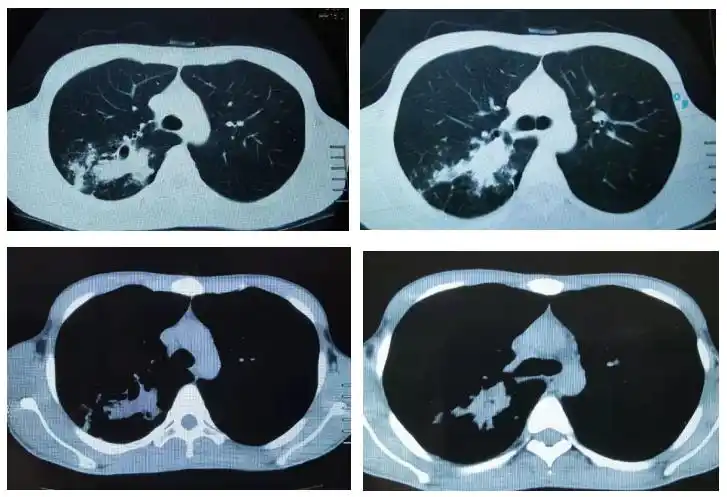

咳嗽咳痰6年小伙吃激素竟吃出肺结核